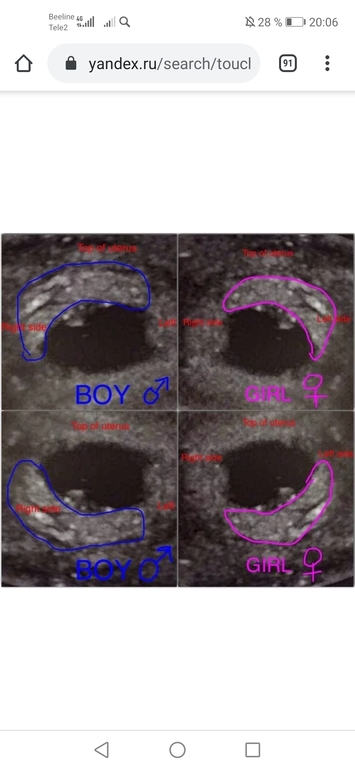

Метод Рамзи

Пол малышаДевочки, кто разбирается, посмотрите, пожалуйста, мальчик или девочка по методу Рамзи? УЗИ вагинальное.

А мне кажется девочка ☺️ потому что и эмбрион и хорион расположены больше справа по снимку, то есть в реале слева 😁 что соответствует женскому полу по данному методу. Но как и у любого метода бывают погрешности, но я за девочку)))))